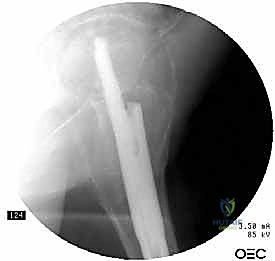

1. المسمار النخاعي الرئيسي (Intramedullary Nail): مسمار طويل يمتد داخل القناة النخاعية لعظمة الفخذ.

2. المسمار الرأسي/العنقي (Cephalic/Lag Screw): مسمار سميك وقوي يمر من خلال الجزء العلوي للمسمار النخاعي، ويدخل في عنق ورأس عظمة الفخذ لتثبيت الكسر الرئيسي.

3. مسامير الغلق السفلية (Distal Locking Screws): مسامير صغيرة تُثبت أسفل المسمار النخاعي لمنعه من الدوران أو الانزلاق داخل العظم.

هذا التصميم العبقري يجعله أقوى نظام تثبيت متوفر حالياً، حيث يمر محور تحمل الوزن عبر المسمار الموجود داخل العظم، مما يجعله مقاوماً للكسر والانحناء، ويسمح للمريض بالاعتماد على ساقه في وقت قياسي.

6. التثبيت السفلي (Distal Locking)

لضمان عدم دوران العظمة حول المسمار، يتم إدخال مسمار أو مسمارين صغيرين في الجزء السفلي من المسمار النخاعي عبر شقوق جلدية دقيقة جداً (لا تتجاوز 1 سم).